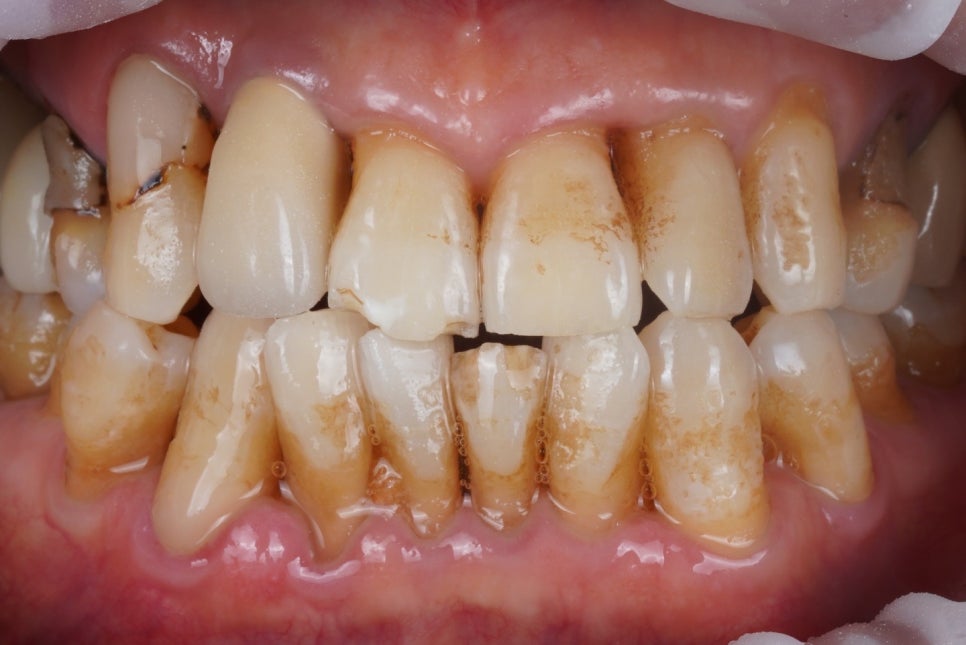

출처 아카이브 열기다소 불편할 수 있는 사진을 한 장

보여드리겠습니다.

오늘은 좀 보기 거북할 수 있는 사진이

몇 장 올라갈 예정입니다.

그러나 전후 차이는 확실한만큼

심호흡 한 번 하시고 시작해보겠습니다.

이분은 치아가 닳고 깨진 것도 문제이지만

그것보다는

뿌리가 드러난 치아들,

'잇몸 내려앉음'이라고 표현할 수 있는

치주질환이 더욱 문제인 경우였습니다.

그런데 환자분께서는 당장

입을 벌릴때나 웃을 때

예전에 해놓은 치경부레진 변색이나

치아에 낀 착색물질(치아 때)이

거슬려서 저희 치과를 방문해주셨는데요,